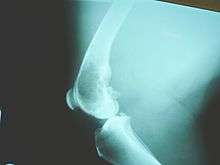

Osteosarcomas tend to occur at the sites of bone growth, presumably because proliferation makes osteoblastic cells in this region prone to acquire mutations that could lead to transformation of cells (the RB gene and p53 gene are commonly involved). Due to this tendency, high incidence of osteosarcoma is seen in some large dog breeds (St. Bernards and Great Danes). The tumor may be localized at the end of the long bone (commonly in the metaphysis). Most often it affects the proximal end of tibia or humerus, or distal end of femur. Osteosarcoma tends to affect regions around the knee in 60% of cases, 15% around the hip, 10% at the shoulder, and 8% in the jaw. The tumor is solid, hard, irregular ("fir-tree," "moth-eaten", or "sun-burst" appearance on X-ray examination) due to the tumor spicules of calcified bone radiating in right angles. These right angles form what is known as Codman's triangle, which is characteristic but not diagnostic of osteosarcoma. Surrounding tissues are infiltrated.

Family physicians and orthopedists rarely see a malignant bone tumor (most bone tumors are benign). The route to osteosarcoma diagnosis usually begins with an X-ray, continues with a combination of scans (CT scan, PET scan, bone scan, MRI) and ends with a surgical biopsy. A characteristic often seen in an X-ray is Codman's triangle, which is basically a subperiosteal lesion formed when the periosteum is raised due to the tumor. Films are suggestive, but bone biopsy is the only definitive method to determine whether a tumor is malignant or benign.